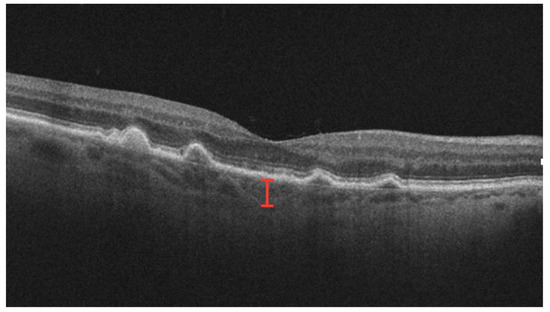

3.3. Outer-Retinal Damage

3.4. Hyper-Reflective Material